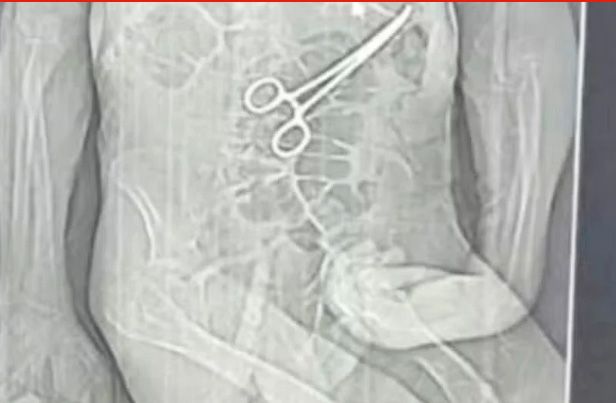

Família de Manoel Cardoso de Brito acusa a unidade de saúde de erro médico e afirma que uma pinça cirúrgica foi esquecida dentro do corpo do paciente após o primeiro procedimento

A família de Manoel Cardoso de Brito acusa a unidade de saúde de erro médico e afirma que uma pinça cirúrgica foi esquecida dentro do corpo do paciente após o primeiro procedimento.

Após a morte, a família teve conhecimento de uma tomografia divulgada por uma rádio local que indicaria a presença de uma pinça cirúrgica dentro do corpo do paciente. Segundo o advogado dos familiares, Iuri Evangelista Furtado, a partir desse exame começaram a ser adotadas medidas legais.